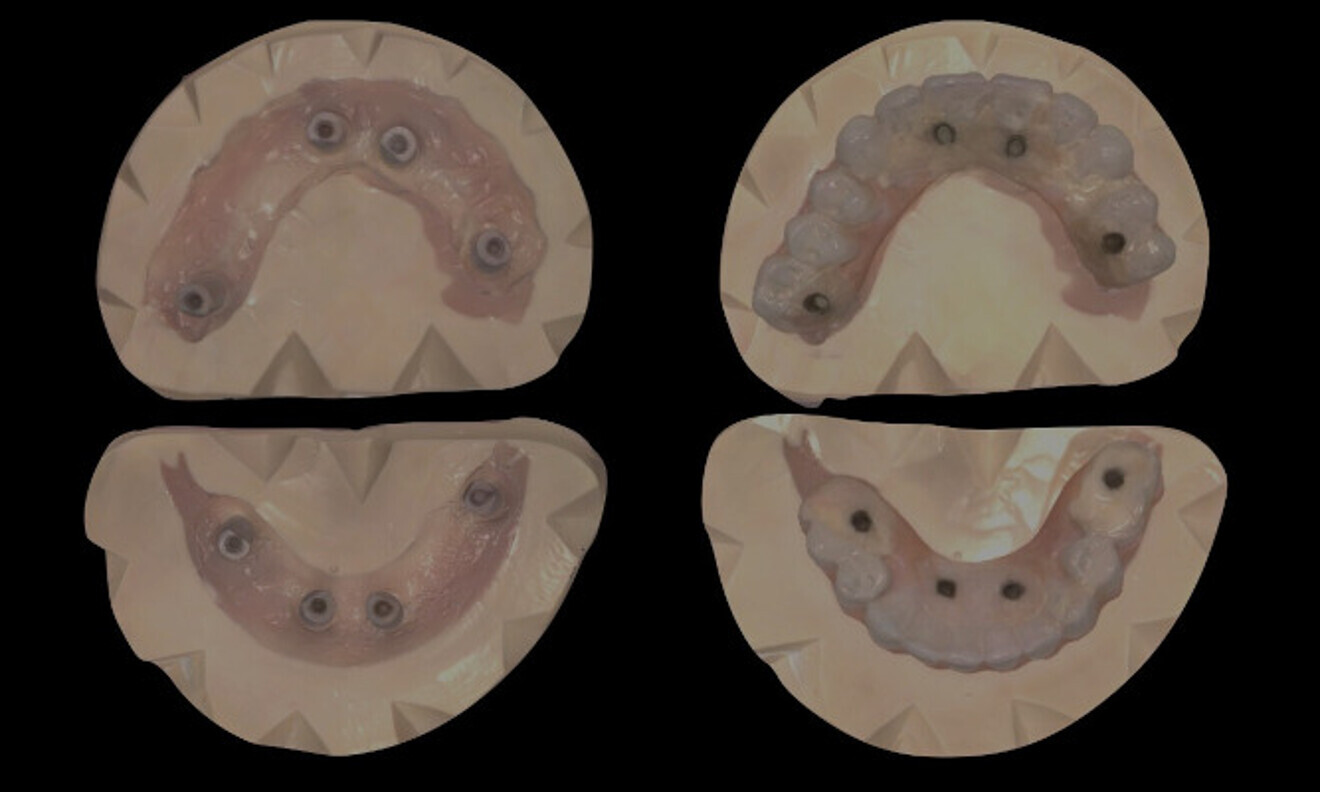

The patient was followed up, and at six months after implant placement, an indirect digitisation of the back-poured master cast was done, allowing for superimposition of the tooth position to the implant position (Fig. 11). The final tooth set-up and occlusal scheme were done digitally to ensure optimised aesthetics and function (Fig. 12). Once everything had been digitally verified, the final zirconia prostheses with layered porcelain gingivae were fabricated (Fig. 13). The occlusion was checked, and the patient was given a 3D-printed occlusal splint to protect the implant-supported prostheses, acting as an absorber and distributor of occlusal forces (Fig. 14). A panoramic radiographic was taken to monitor the health around the dental implants at delivery of the prostheses (Fig. 15). The patient was provided with hygiene instructions and scheduled for regular check-ups to ensure ongoing care and monitoring.

Fig. 11